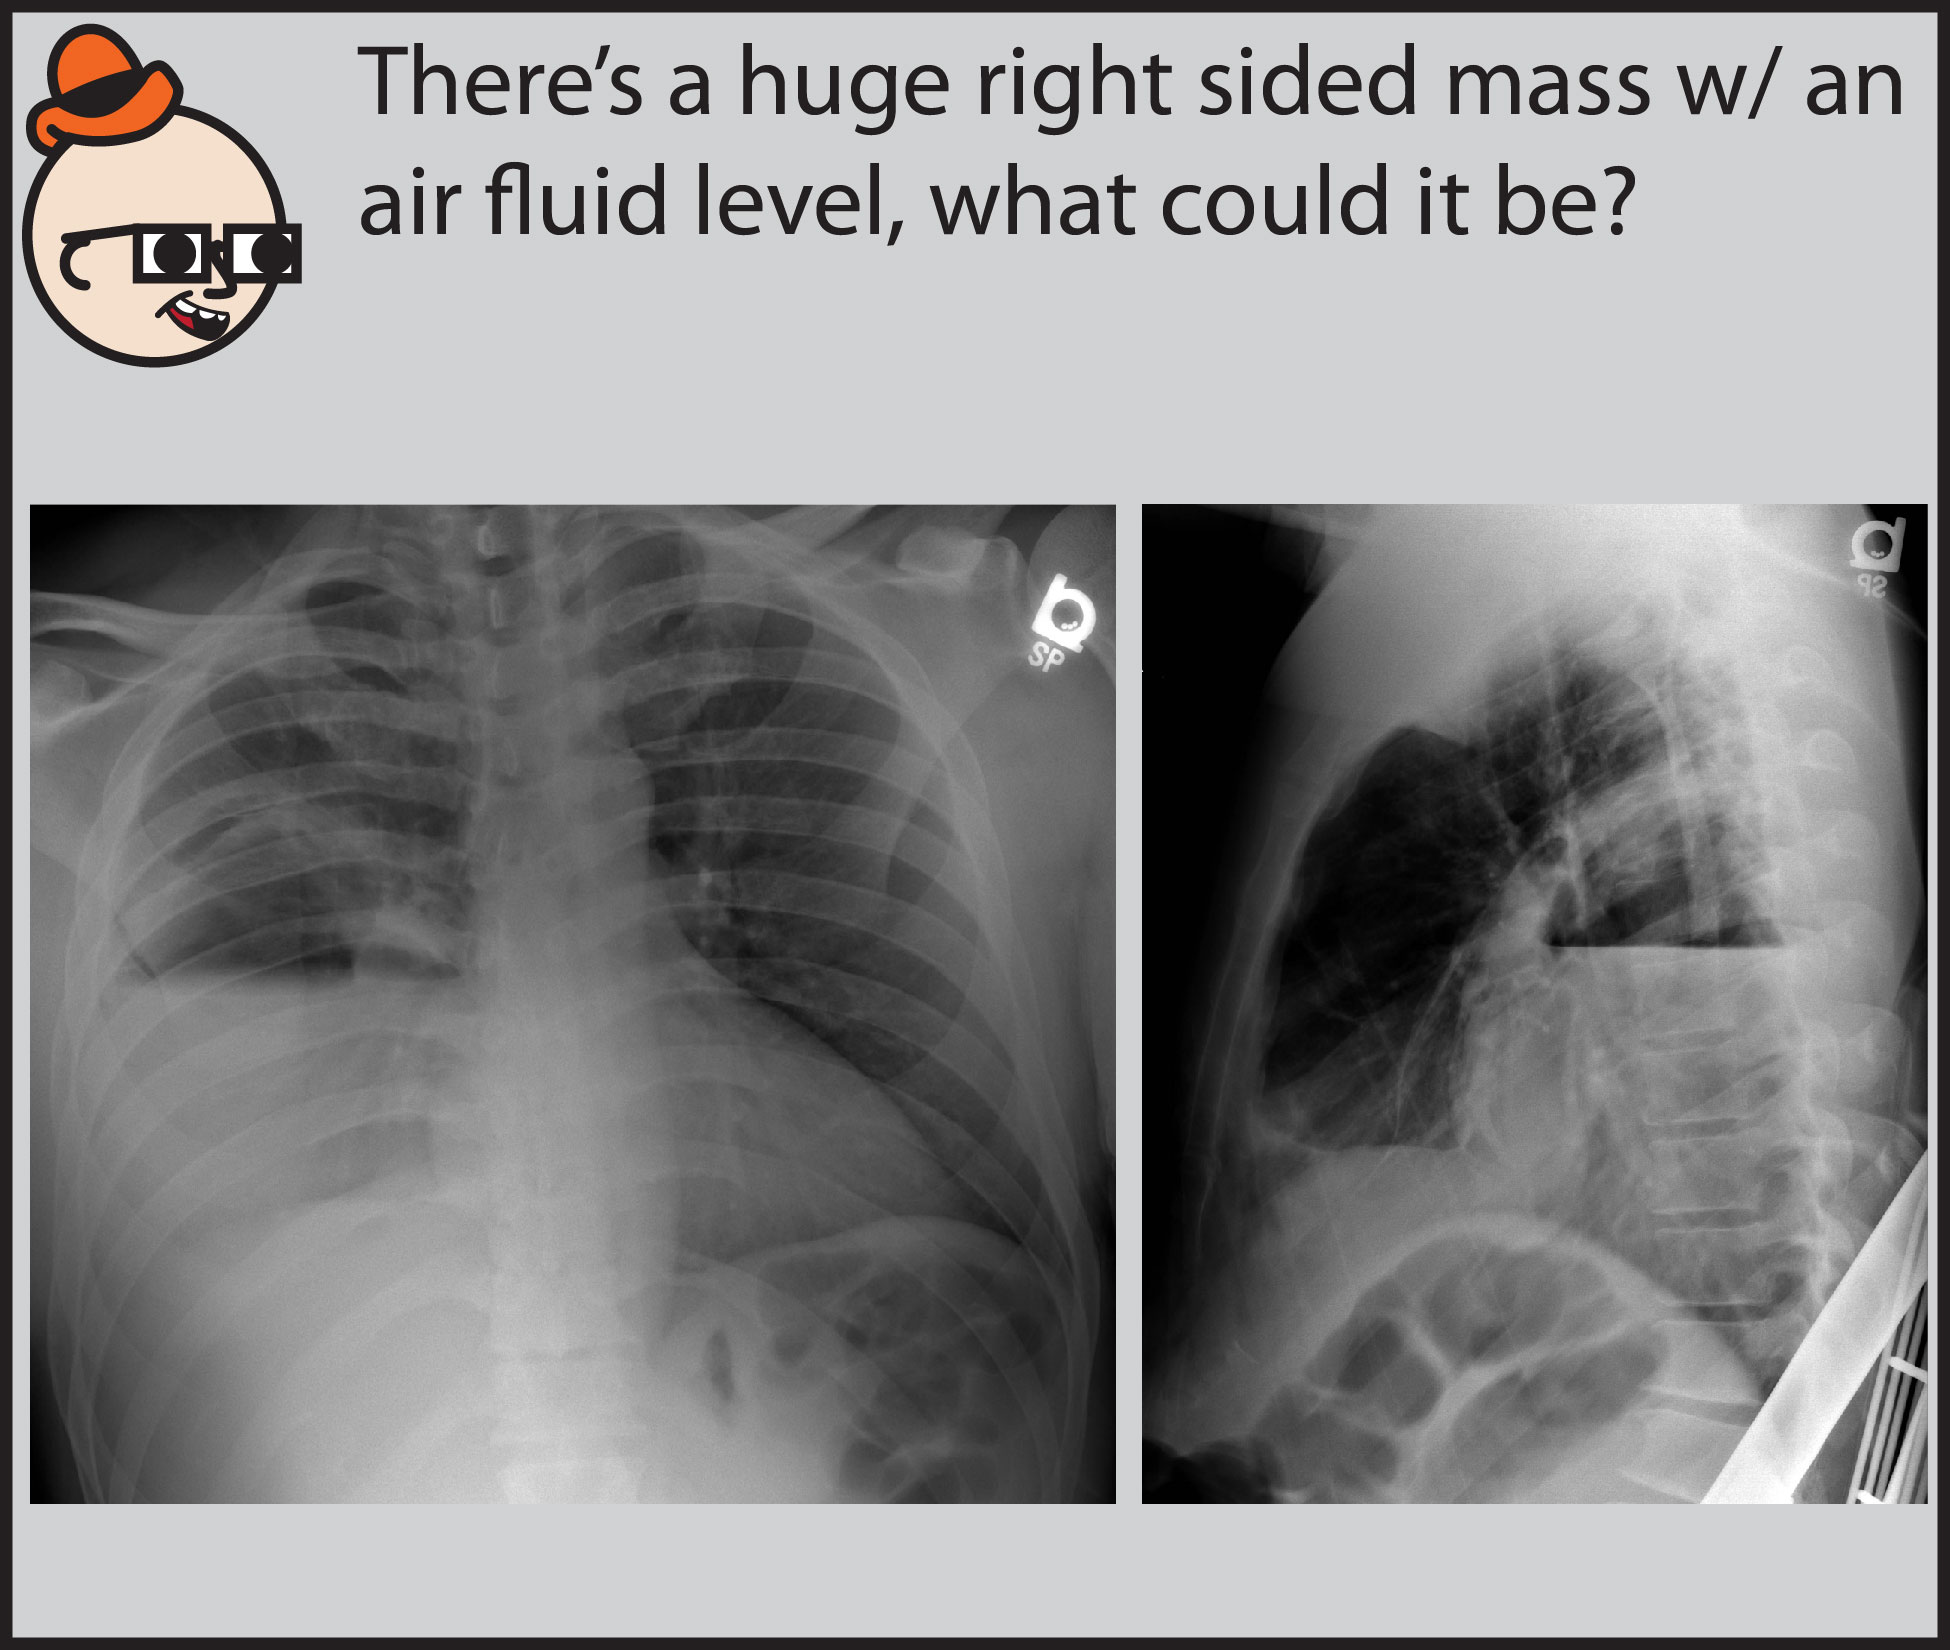

LearningRadiology Lung, Abscess, pulmonary Abscess X Ray Sign early symptoms mimic pneumonia, including fever, chills, cough, night sweats, and chest pain, with a productive cough. learn about the four types of lung abscess, their common causes, clinical presentation, and radiologic features. learn about the causes, symptoms, pathology, radiographic features, treatment and complications of lung. systemically, patients with abscesses can present with swinging pyrexia and. Abscess X Ray Sign.